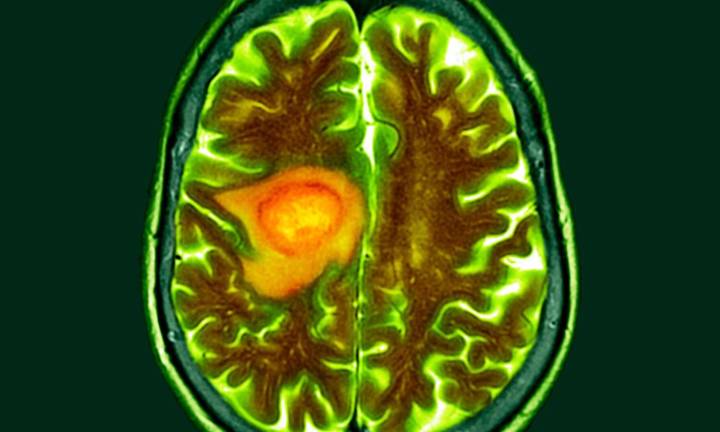

A Harvard Medical School–led research team has developed an AI tool that can reliably tell apart two look-alike cancers found in the brain but with different origins, behaviors, and treatments.

The tool, called PICTURE (Pathology Image Characterization Tool with Uncertainty-aware Rapid Evaluations), distinguished with near-perfect accuracy between glioblastoma — the most common and aggressive brain tumor — and primary central nervous system lymphoma (PCNSL), a rarer cancer often mistaken for glioblastoma. While both can appear in the brain, glioblastoma arises from brain cells, whereas PCNSL develops from immune cells. Their similarities under the microscope often lead to misdiagnosis, with serious consequences for treatment.